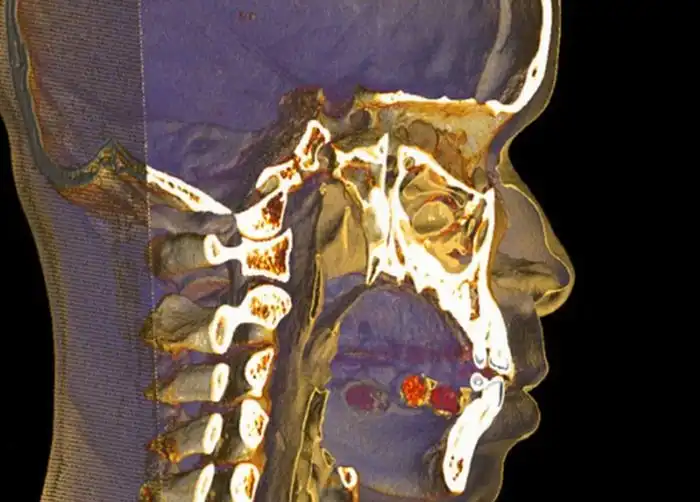

Пакетики с кокаином под языком

Попытка провезти кокаин под языком

Одна часть кокаина под языком, а вторая в желудке